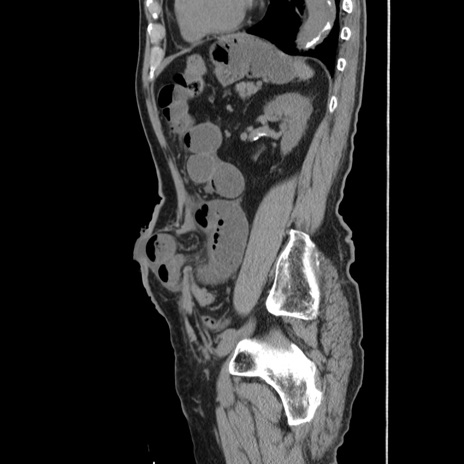

症例24(矢状断像)

【症例】80歳代男性

【主訴】左側腹部痛、嘔吐

【現病歴】本日早朝より左腹部に痛みあり。昼頃嘔吐認めたため、救急要請。

【既往歴】直腸癌(Mile手術)、胆摘

【身体所見】意識清明、BT 35.9℃、BP 221/93mmHg、SpO2 97%(RA) 、腹部:左ストーマ周囲に限局性の腹部膨隆あり。 膨隆部自発痛・圧痛あり・軟。

【データ】WBC 7700、CRP 0.09